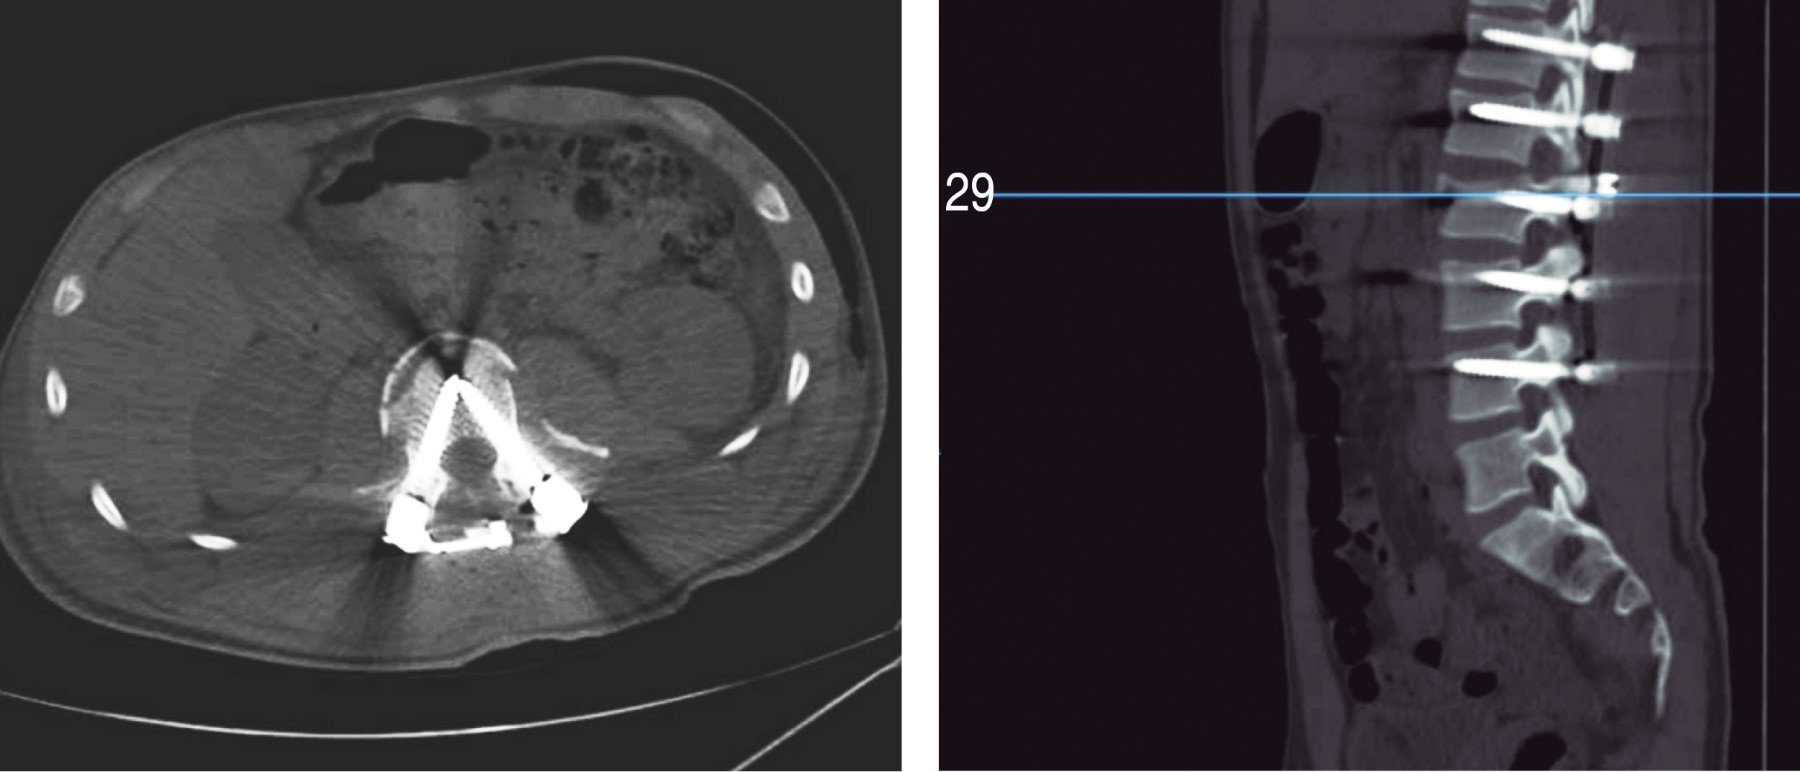

Figure 3